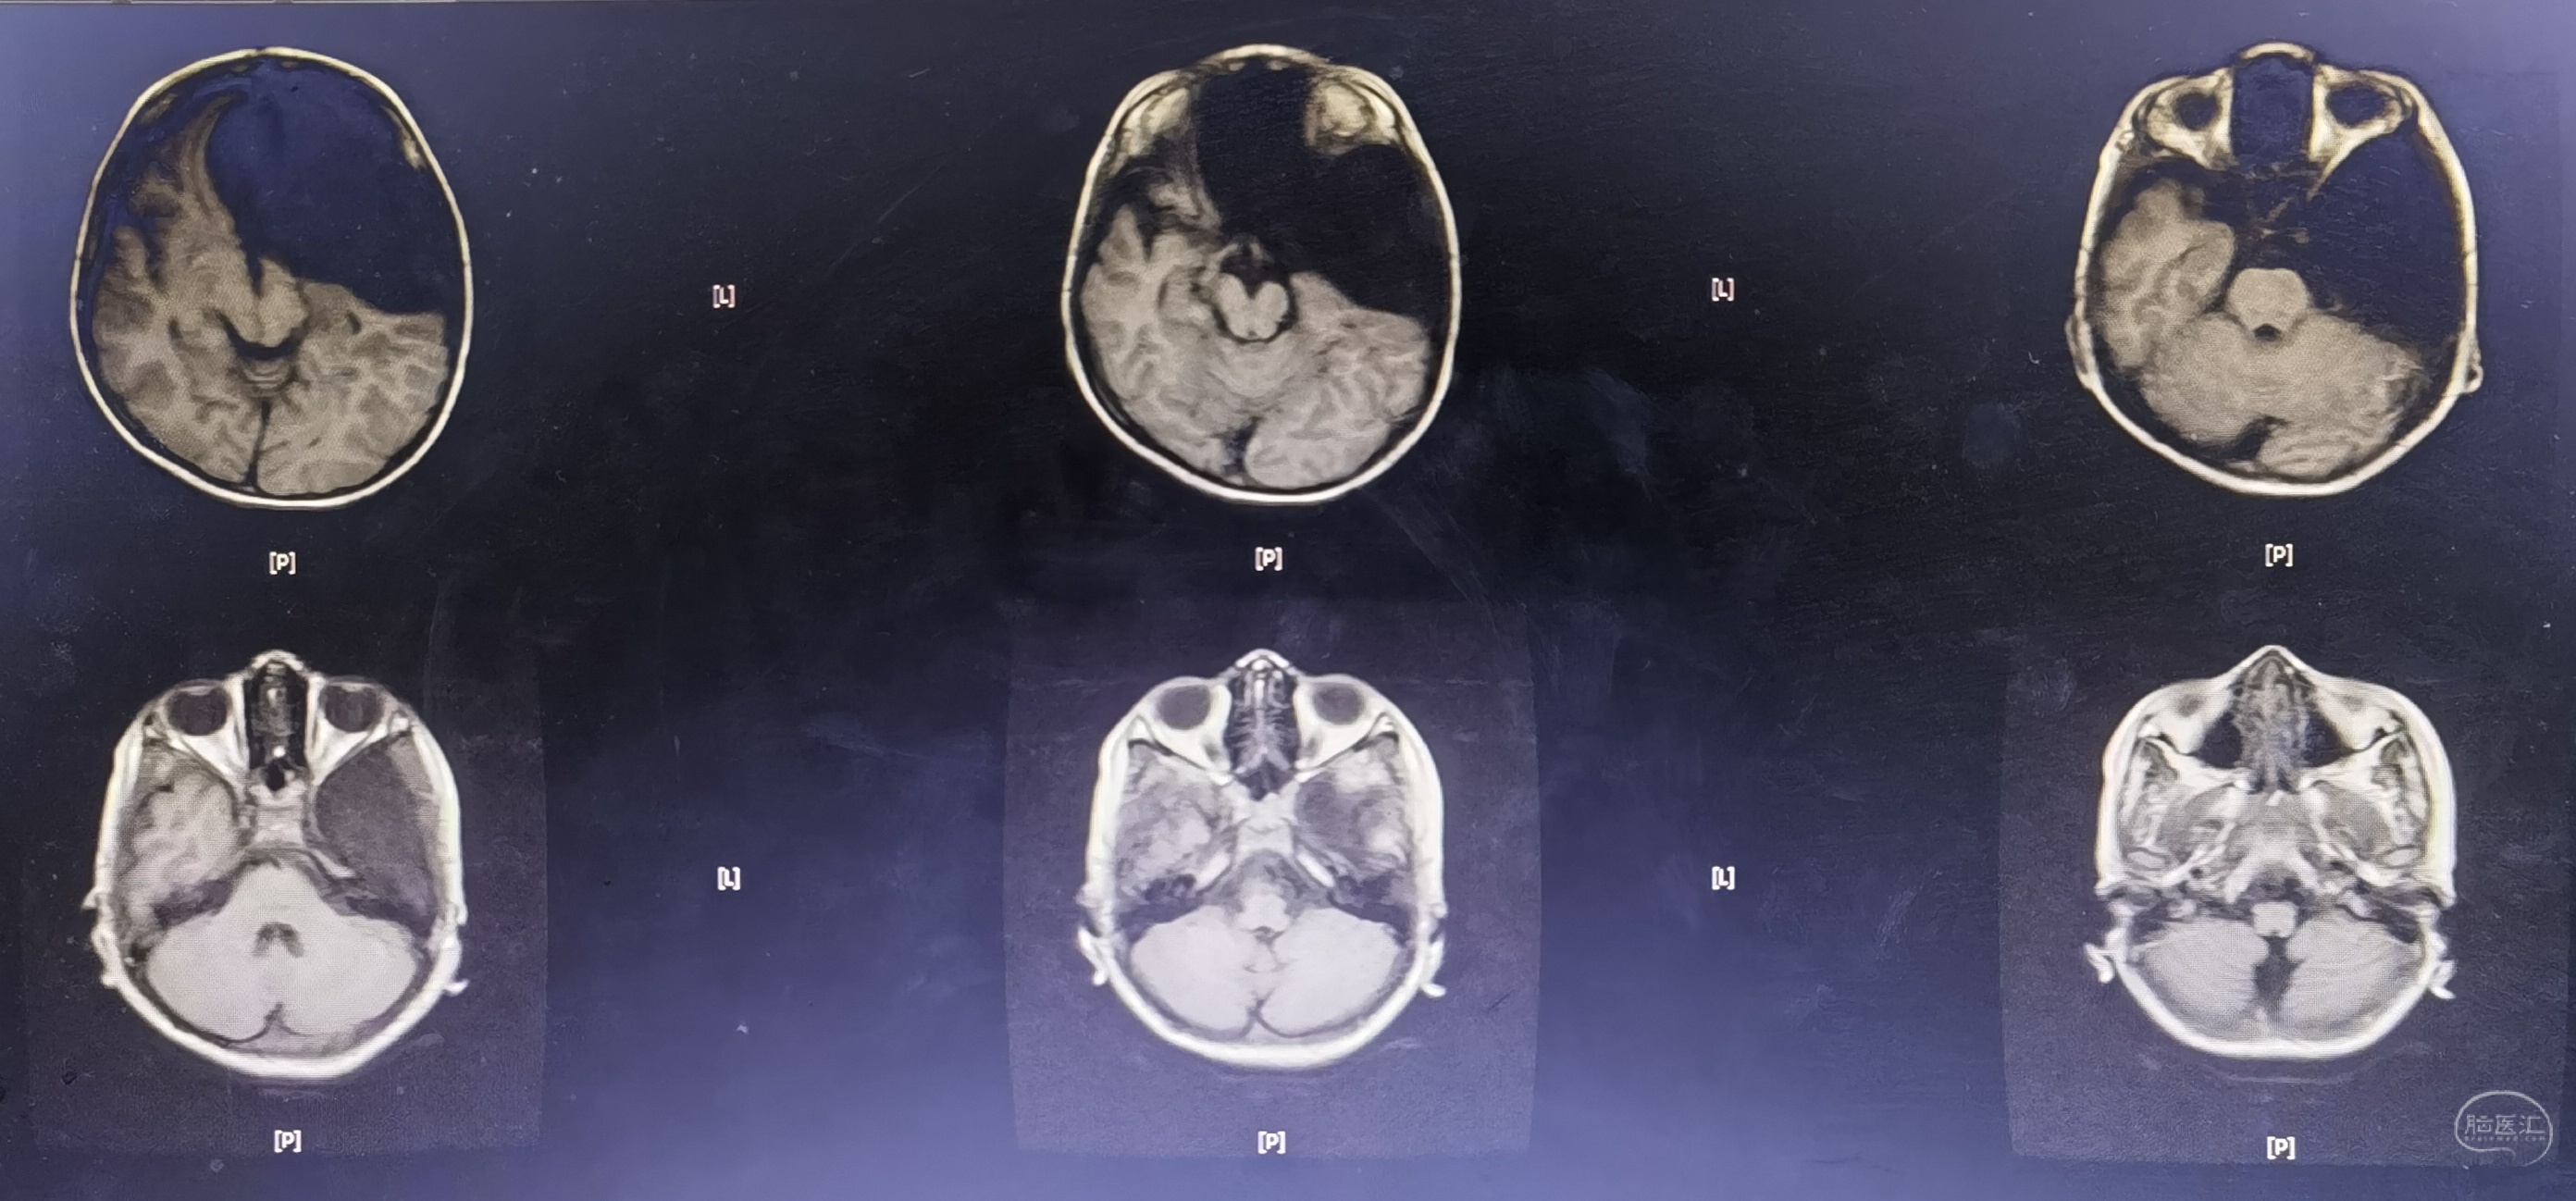

术后CT